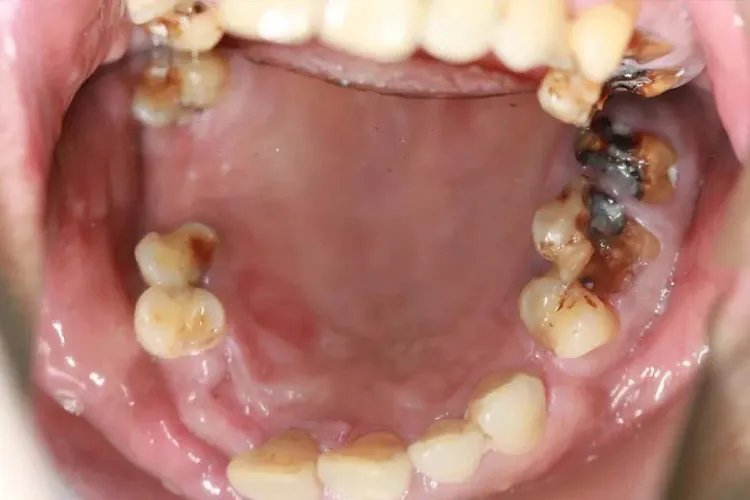

概述蛀牙一般是指龋病,可表现为牙釉质、牙本质和牙骨质颜色、形态和质地的改变。有人认为龋病是由虫子引起,但牙齿里面并没有虫子,而是由微生物、饮食等因素导致。症状临床上龋病一般根据龋损深度分类,可分为浅龋、中龋和深龋,具体症状有所不同:浅龋龋损部位可出现颜色改变,如黑色、白垩色、黄褐色或褐色斑点,多无龋洞形成,用探针检查时有粗糙感或能钩住探针尖端,患者一般无自觉症状,对冷、热、酸、甜刺激亦无明显反应。

病因龋病是牙体硬组织的慢性细菌性、进行性破坏性疾病。龋病的因素主要有宿主、口腔微生物、碳水化合物类食物等。基本发病过程是口腔微生物黏附在牙表面形成牙菌斑生物膜,口腔微生物在牙菌斑生物膜微生态环境中利用糖类食物代谢产酸,并长期堆积在牙表面引起脱矿,形成龋损。早期龋出现牙透明度降低、牙釉质表面呈白垩色改变,继而病变部位色素沉着,局部呈黄褐色或棕褐色,此时尚无牙体缺损。随着破坏的深入,牙体缺损形成龋洞,形如虫蛀,因此人们常称为蛀牙。治疗龋齿的治疗应针对不同的个体制定治疗计划。可通过药物治疗、再矿化治疗、渗透树脂治疗等方法治疗,及时终止病变的发展,做好预防和保护。也可用适当的材料进行充填治疗,或选择嵌体、冠修复等方法恢复牙齿的形态与功能。